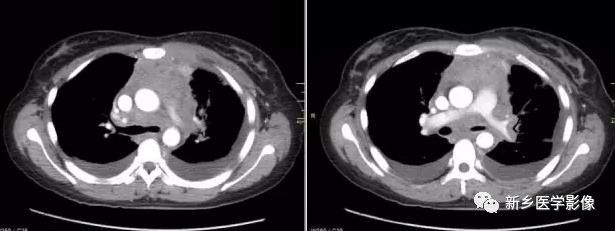

非侵袭性胸腺瘤CT图像

a. CT平扫示前上纵膈主动脉弓与胸骨间软组织密度肿块,密度均匀,边缘浅分叶状 b. CT增强示肿块均匀强化,肿块与主动脉弓之间脂肪间隙清晰